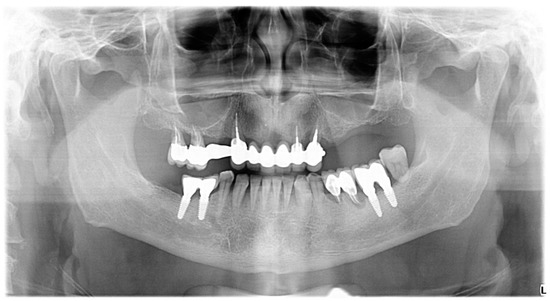

2.4. Radiographic Examination

Radiographic examination was performed on orthopantomograms (e.g., Figure 1 and Figure 2). The dental software Instrumentarium CliniviewTM (Palodex Group Oy Nahkelantie 150, Tuusula, Finland) was used for taking and importing digital radiographs which were analyzed on a large (24′) computer screen. The distance from the implant shoulder to the alveolar bone crest was measured in millimeters at the mesial and distal aspects using the software’s measuring tools [59]. A bone-loss mean value per patient was calculated using the mesial and distal measurements resulting from the crestal bone level (CLB). The mean value per patient of the marginal bone level (MBL) was calculated by measuring, on radiographs, the distance between the CEJ/restoration margin—radiographic bone level at mesial and distal site of each tooth. Unaffected implants were considered implants with the bone level reaching the implant shoulder both on mesial and on distal sites, as viewed on radiographs. Minimally affected implants were considered implants in which the bone level reached one millimeter below the implant shoulder, as viewed on the radiographs (Figure 2 and Figure 3).

Figure 2. Patient’s radiograph at the beginning of SPT.

Figure 3. Unaffected implants (reg. 3.6, 3.7, 4.5, 4.6) in a patient with progressive periodontitis.